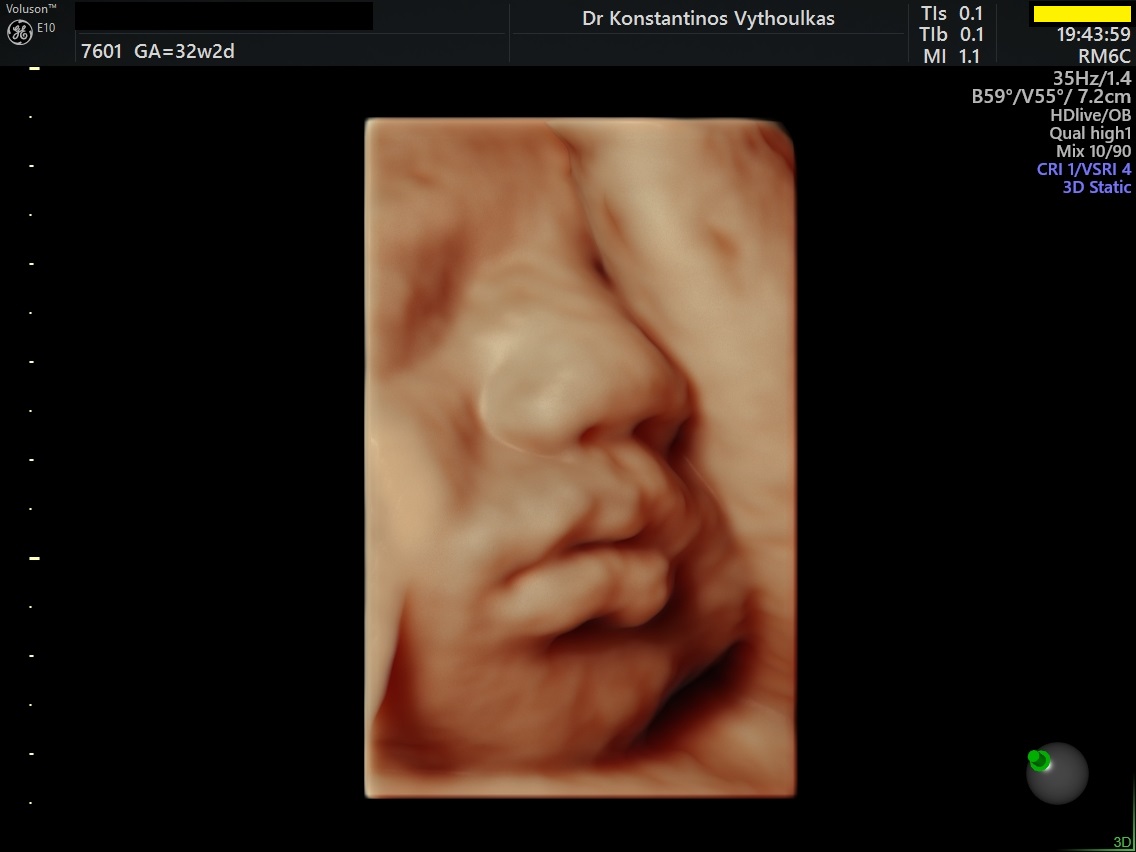

Φωτογραφίες από το αρχείο και από το χώρο του ιατρείου του γυναικολόγου Βυθούλκα Κωνσταντίνου, καθώς και του εργαστηρίου της κυτταρολόγου Λιβέρη Κατερίνας.